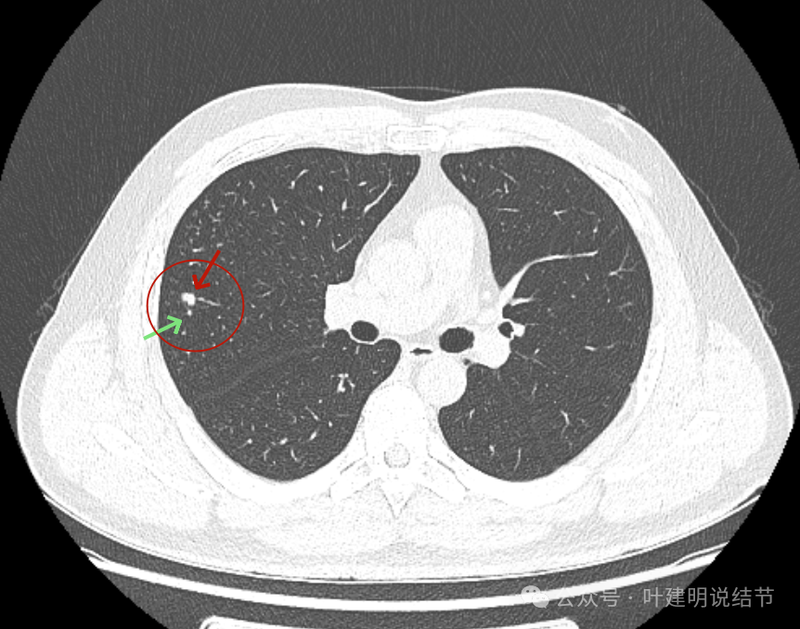

密度高,表面不平不光滑,边上有小的点状高密度的卫星灶似的。

血管征明显。

边缘区显得毛糙。